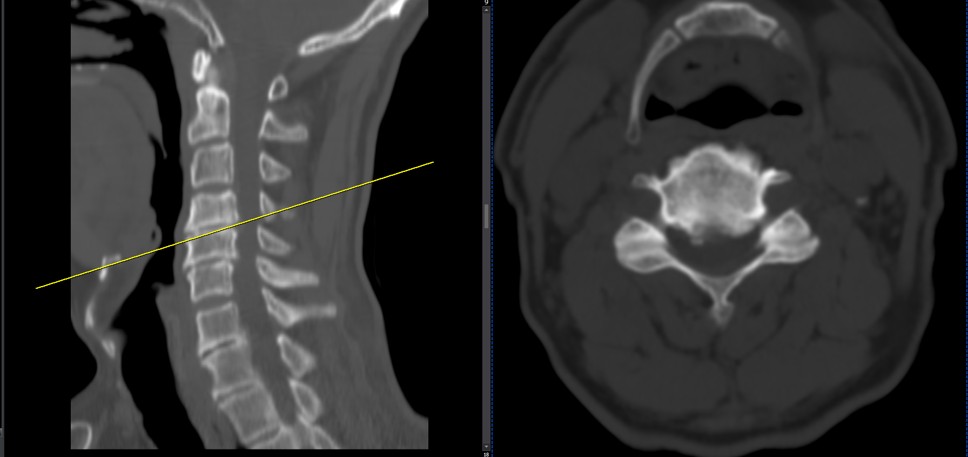

41 years old man presented to my clinic in October 2023 with acute and sever R neck pain with radicular pain to his R upper extremity along C6 dematom since 2 weeks ago. Examination didn’t show any upper motor signs. Was suggested urgent surgery

I ordered EMG/ NCV : showed mild R C6, C7 irritation without any active axonal loss

In his MRI was reported R. para R. IVF Massive extrusion. I decided to control his pain and manage this patient with reevaluation of patient every other session. For 5 sessions i just used acupuncture and laser and IFC and mild adjustments to his R. T3-T7 and mild arthosteem to above and below involved segment. Cervical adjustment considered contraindicated for this patient. From session 6th- 8th i started to use mild/gentle cervical decompression. He used soft cervical collar all the time. His pain decreased by 80 percent

I gave him cervical traction pump to be used 3-5 times per day at home for the next 3 months and i released the patient. He was evaluated every week once for one month and after that every 2 weeks. After 3 month I repeated MRI. Size of the herniated disc was reduced greater than 50 percent. Asked him to do another mri in 6 months

MRIs before and after proper management of this patient: